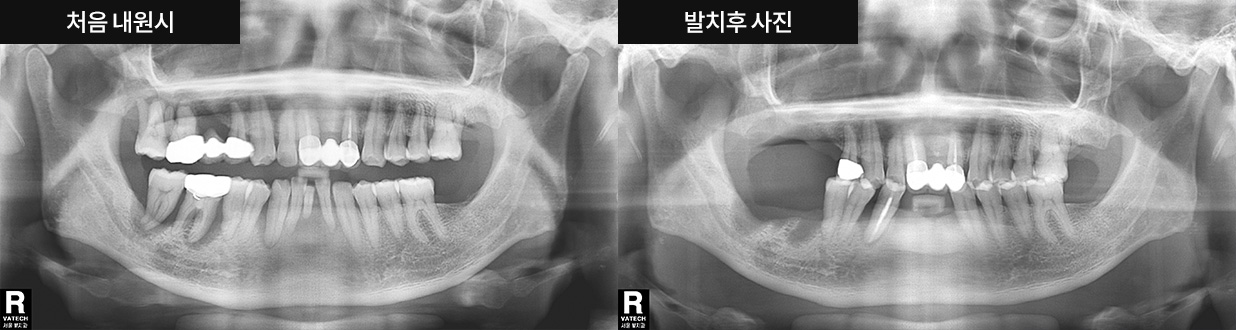

최근 임플란트의 경향은 임플란트로 소요되는 시간을 최소로 줄이고자 하는 것으로 치아를 발치한 후 바로 임플란트를 식립하는 1 day 임플란트 방법이 자리 잡고 있습니다.

임플란트를 식립하는 지연 임플란트와 비교해도 성공률이 뒤지지 않는 것이 1 day 임플란트입니다.